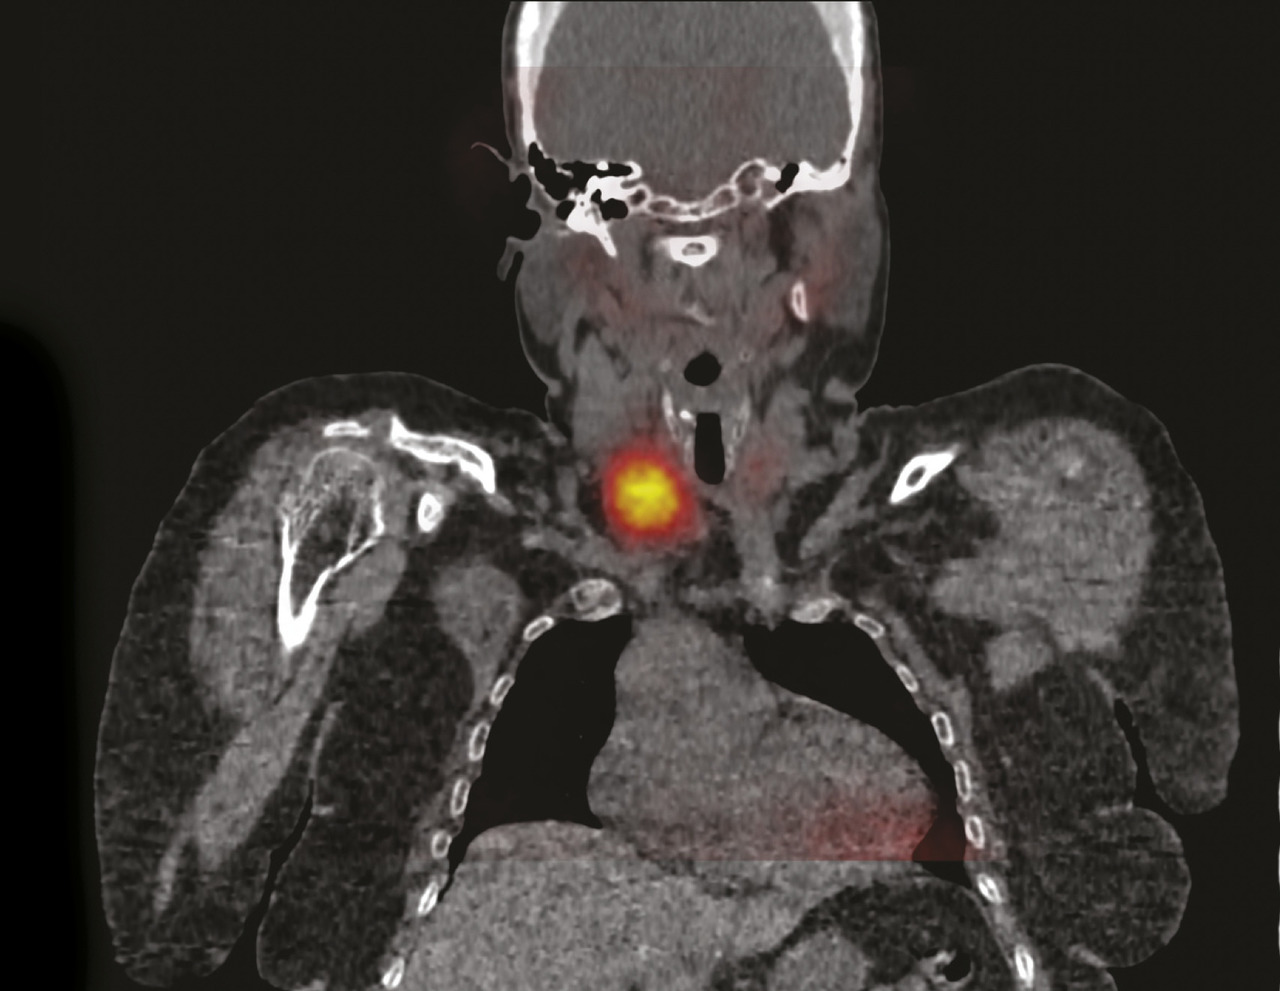

Cette patiente congolaise de 61 ans consultait pour des douleurs lombaires mécaniques anciennes très invalidantes. Les radiographies montraient une déminéralisation osseuse diffuse. La tomodensitométrie du bassin montrait une ostéolyse très particulière des deux sacro-iliaques (fig. 1) ainsi que des lésions fibrokystiques de l’aileron sacré droit (fig. 2). La calcémie était à 3,81 mmol/L, la parathormone était à 1 300 pg/mL (N : 6-50 pg/mL) confirmant le diagnostic d’hyperparathryoïdie primaire. La scintigraphie parathyroïdienne localisait une formation macronodulaire intensément fixante de 30 mm de grand axe au pôle inférieur du lobe thyroïdien droit (fig. 3). La patiente bénéficiait d’une parathyroïdectomie inférieure droite sous anesthésie locale, la calcémie se normalisait en 15 jours et les douleurs s’amélioraient en 3 mois.